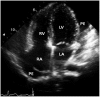

Pneumopericardium is a rare complication of pericardiocentesis, occurring either as a result of direct pleuro-pericardial communication or a leaky drainage system. Air-fluid level surrounding the heart shadow within the pericardium on a chest X-ray is an early observation at diagnosis. This clinical measurement and process is variable, depending on the hemodynamic status of the patient. The development of a cardiac tamponade is a serious complication, necessitating prompt recognition and treatment. We recently observed a case of pneumopericardium after a therapeutic pericardiocentesis in a 20-year-old man with tuberculous pericardial effusion.